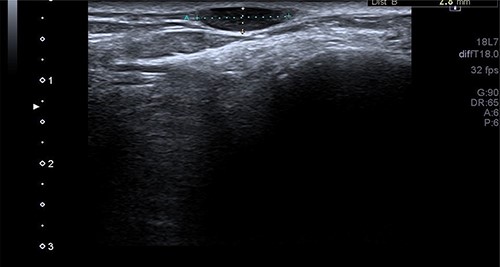

A 50-year-old lady presented to us with a lump in her left foot on the lateral aspect at the level of the calcaneocuboid joint for a 1-year duration, which was associated with pain. She consulted her GP who advised an US scan. This revealed a lump over the dorsum of the left foot on the lateral side. She also had a magnetic resonance imaging (MRI) scan which was indeterminate (Figs 3 and 4). It was reported as a suspected sarcoma. She was then referred to the Sheffield sarcoma unit where she underwent a biopsy of the swelling; which was reported as angiomyolipoma (a benign swelling). She was not keen on excision initially, but as the swelling increased in size and started becoming painful, she underwent an excision of the lesion under our care and the histopathologic examination of the excised sample confirmed it to be angioleiomyoma. The post-operative period was uneventful and she was discharged from our care after 10 weeks. At this time, she was symptom-free and had a pain score of 0/10.

T1 MRI image of the soft tissue lesion over the lateral foot in Patient 2, which shows a lesion isointense to hypointense to the muscle.

Similarly, in Case 2, the patient had an MRI scan which reported an indeterminate swelling suggestive of a possible sarcoma. As the MRI findings were not characteristic of the MRI findings of an angioleiomyoma, such as T1: isointense or hyperintense to muscle, T2: heterogeneous and slightly hyperintense to muscle and T1 C+ (Gd): homogenous to heterogeneous enhancement, suspicion of the sarcoma was reported from the MRI scan findings and referral to sarcoma unit was advised. This clearly shows that the US and the MRI scan findings can suggest a different diagnosis, and a confirmed diagnosis was only established following excision and histopathological examination of the excised lesion. Usually, angioleiomyomas have a peripheral low-intensity signal rim corresponding to a fibrous pseudo capsule with adjacent vascular structures with isointense or hypointense to muscle on T1 images and heterogeneous and slightly hyperintense to muscle on T2 images.